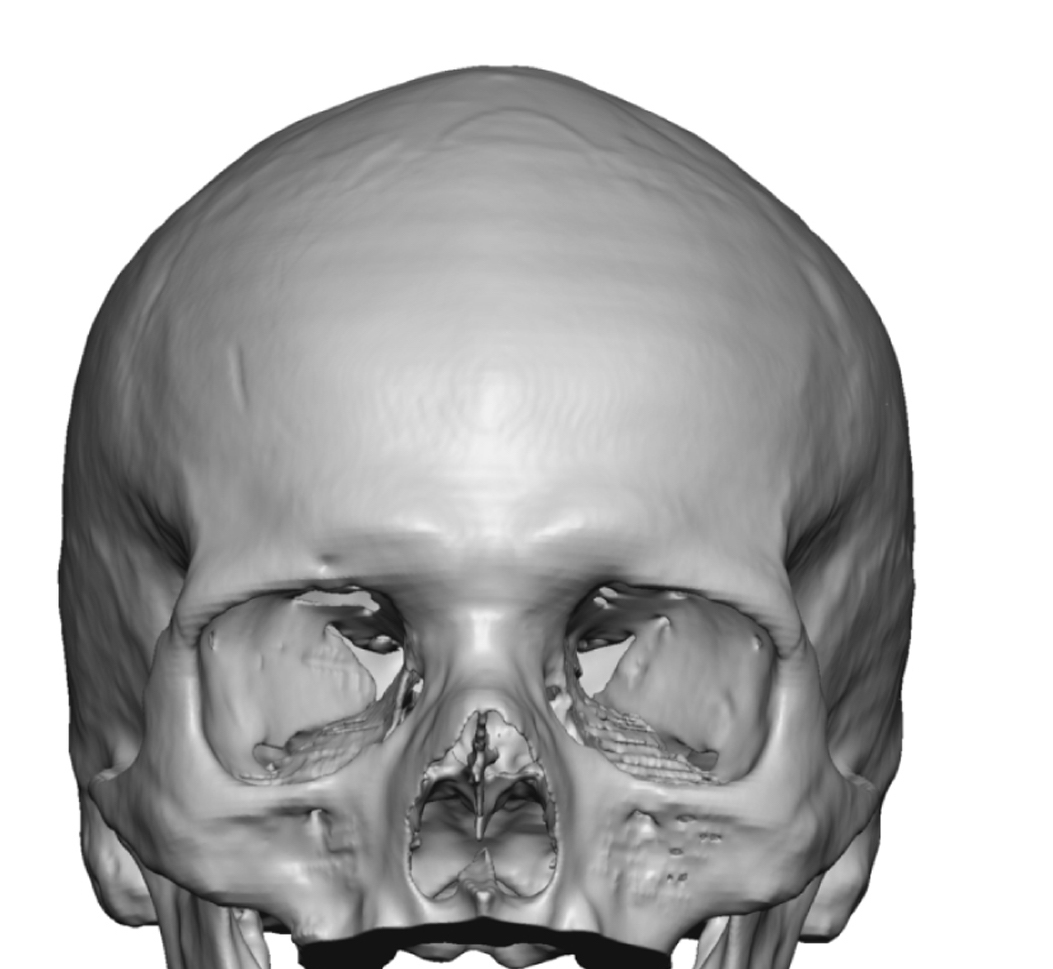

Patient 84

Desire for change of head shape from front view form an inverted V shape to a rounder and wider head shape.

Placement of custom extended forehead-temporal implants through incisions in the crease behind the ear. (he had a prior back of head skull implant which is green in the implant designs and which the head widening implants partially covered it)

Desire for change of head shape from front view form an inverted V shape to a rounder and wider head shape.

Placement of custom extended forehead-temporal implants through incisions in the crease behind the ear. (he had a prior back of head skull implant which is green in the implant designs and which the head widening implants partially covered it)